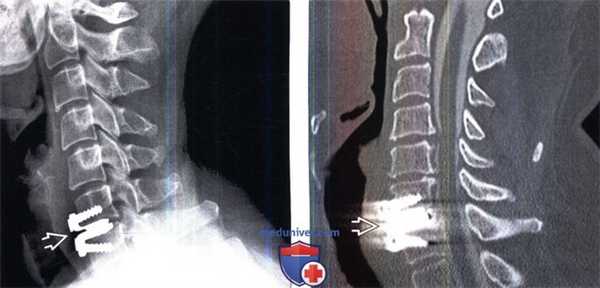

(Слева) Рентгенография шейного отдела позвоночника в боковой проекции: случай корпорэктомии С4 с замещением тела позвонка кейджем и стабилизацией С3-С5 сегмента вентральной пластиной. Подобные сетчатые кейджи выбираются исходя из размеров замыкательных пластинок и высоты дефекта. На этом снимке видны признаки некоторого коллапса тела С5 с проседанием в дефект пластины и кейджа.

(Справа) На рентгенограмме в прямой проекции и фронтальном КТ-срезе визуализируются парные кейджи Pyramesh, использованные для реконструкции коллабированного тела L2 позвонка. Вокруг кейджей визуализируется метилметакрилат.